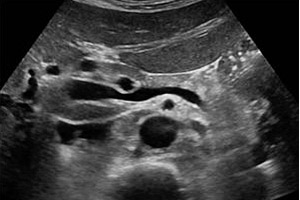

УЗИ забрюшинных лимфоузлов (или паравертебральных лимфатических узлов) – это процедура, при которой с помощью ультразвуковой волны врач оценивает состояние и структуру лимфатических узлов, расположенных в забрюшинном пространстве.

УЗИ лимфатических узлов забрюшинного пространства используется для диагностирования и оценки различных заболеваний, связанных с лимфатической системой.